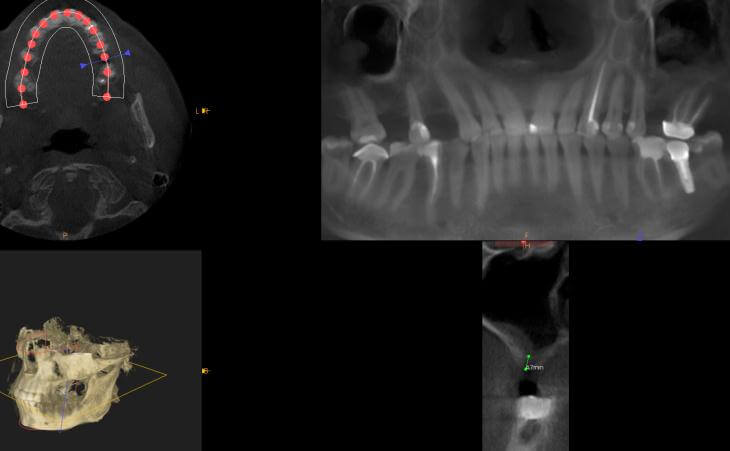

Patient presented with multiple areas of right and left upper jaw tooth loss for years and subsequent bone resolution. The patient underwent bilateral sinus lift procures and ridge grafts for future implant placement

Patient has been missing right and left upper teeth for many years. Bone has deteriorated and a CT scan showed insufficient bone volume for implant placement. The patient underwent Bilateral Sinus Lift surgery and Bone regeneration.

Patient has been missing all her upper teeth and has worn an upper denture for the past 20+ years. The patient underwent Bilateral Sinus Lift surgery and Bone regeneration.

44 year old male missing right and left upper teeth for years decided to have implants placed to replace his upper denture. CT scan determined there was advanced bone loss in the upper jaw under his sinus cavities. Bilateral Sinus Lift Bone Graft was performed for implant placement.